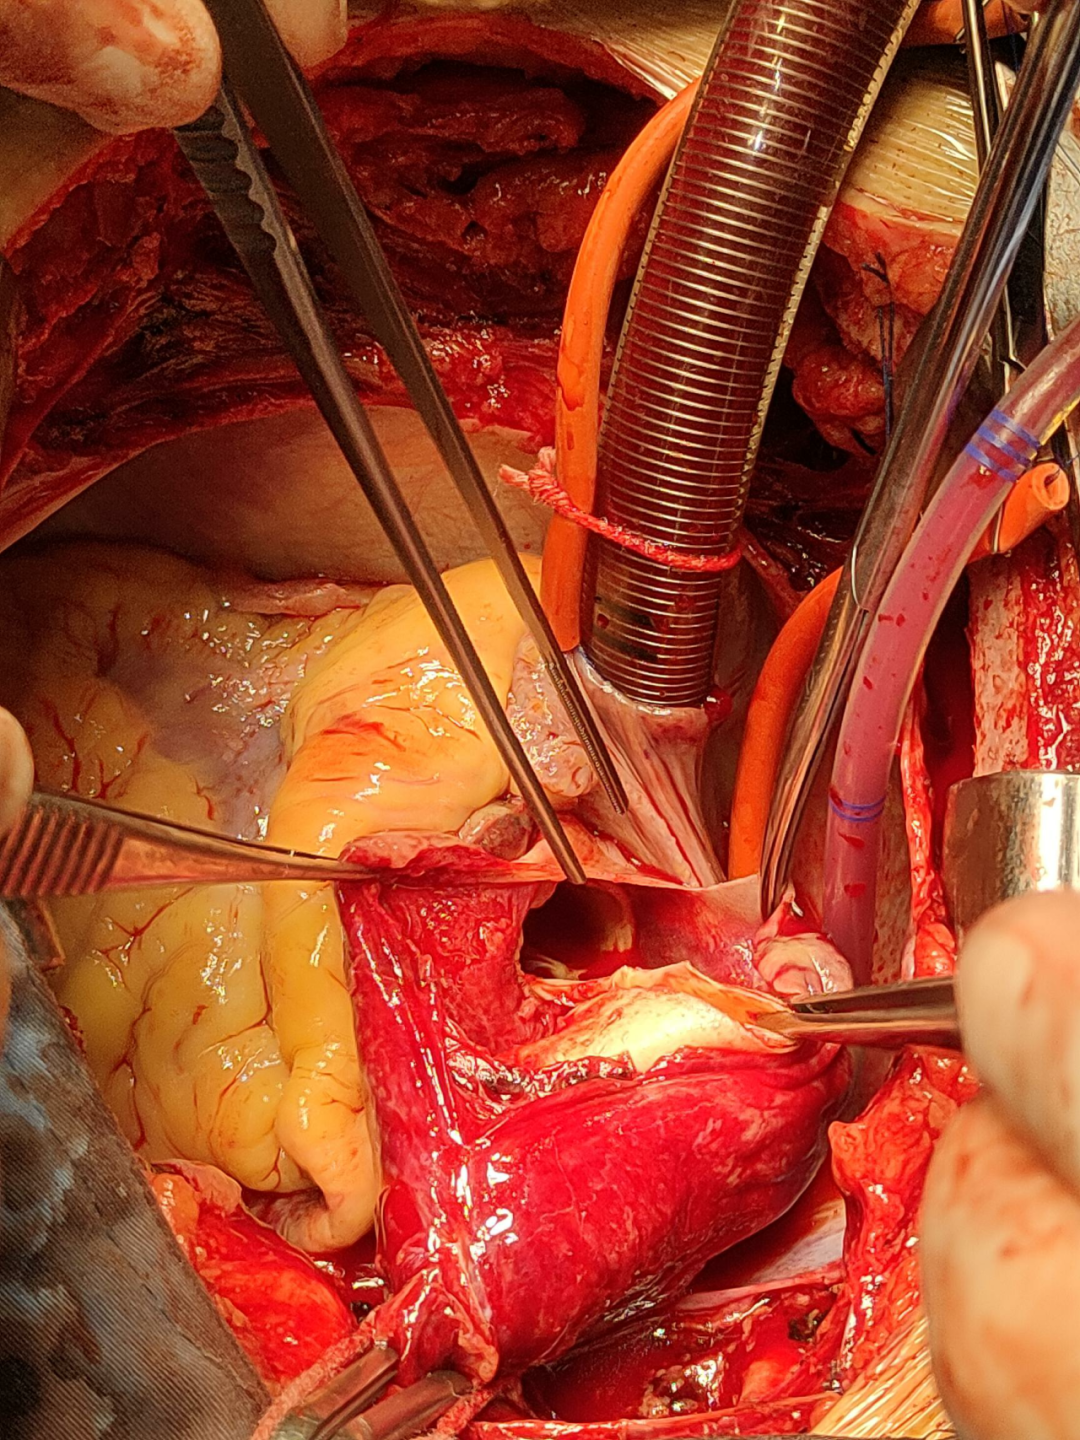

列入商议的有麻醉科、超声科、手术室、监护室及心脏大血管外科的医护人员,人人就这个病人纷纷揭橥了本身的定见,商议的核心还在手术的时机上,认为自动脉夹层的手术自己出血的风险就大,加之患者口服了两种冲击量的抗凝药物,如今手术出血的风险就更大了。而急性A型自动脉夹层是人类最凶险的疾病之一,在其发病后其灭亡率每小时增加1%,若患者发病48小时内不成急诊手术灭亡率为50%,2周内不手术病死率约75% 。对患者来说,灭亡随时降临。张晶副院长在综合人人的定见后,决意率领团队急诊给患者行手术治疗,“如今手术更能给患者带来生的进展!固然风险较其他夹层手术高”,张晶副院长如是说。 经与眷属充裕沟通,赞成手术!

一切都在心脏大血管外科团队医护人员的手下重要而有序地进行。手术历时9个小时,顺利完成“升自动脉置换+全弓置换+支架象鼻手术”。在医护人员的配合治理下,患者于术后12天顺利出院。全体医护人员都为患者和眷属感应由衷地愉快。